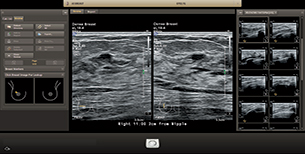

Функция интеллектуального определения анатомических структур изучает данные УЗИ пациента и применяет адаптивную интеллектуальную логику системы с использованием трехмерных анатомических моделей для создания более простых и воспроизводимых результатов. Инструменты интеллектуального определения анатомических структур, например HeartModel, используют усовершенствованное моделирование органов, формирование срезов изображений и надежный количественный анализ, помогая упростить проведение УЗИ, обеспечивая более высокую воспроизводимость, предоставляя при этом клиническую информацию нового уровня для решения экономических и клинических задач, возникающих в условиях современного медицинского учреждения.